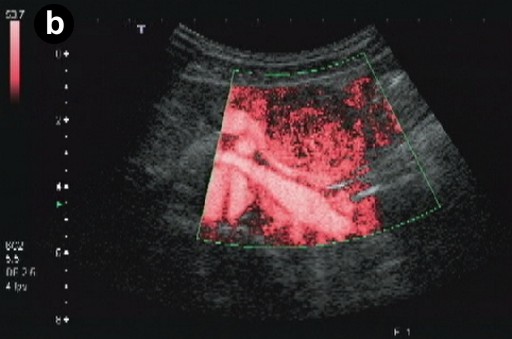

A 66-year-old Japanese woman was admitted to our hospital with a pancreatic tumor indicated in medical examinations. There was no remarkable past history of disease. No inherited factors or marked diseases in her family were noted. On admission, she had no complaints, and physical examinations and laboratory data revealed no noticeable abnormalities. Serum levels of CA 19-9 and s-pancreas-1 (pancreatic associated) antigen were within the normal range. Magnetic resonance imaging (MRI) revealed a mass, 3 cm in diameter, in the body of the pancreas, showing hypointensity on T1-weighted images, marked enhancement after gadolinium diethylenetriaminepenta acetic acid (Gd-DTPA) administration, and mixed hypo- and hyperintense patterns on T2-weighted images (Figure 1abc). Magnetic resonance cholangiopancreatography (MRCP) and endoscopic retrograde cholangiopancreatography (ERCP) showed no abnormal findings. The results of bacterial cultures of the pancreas juice were negative. Computed tomography (CT) revealed a 3 cm solid and cystic tumor within the body of the pancreas, with high resorption CT levels of the cystic components (Figure 1d). Contrast-enhanced CT showed partial enhancement of the solid components, and the main pancreatic duct was not involved in the tumor. Ultrasonography (US) and endoscopic ultrasonography (EUS) revealed a 3 cm solid and cystic tumor with low echoic margins in the body of the pancreas (Figure 2a). Contrast-enhanced US with Levovist® (Bayer Schering, Berlin, Germany) showed partial enhancement of the solid components (Figure 2b). Angiography showed no abnormal findings. From these imaging findings, mucinous cystic neoplasms or acinar cell tumors were considered.

Figure 2. a. US reveals a solid and cystic tumor with low echoic margin in the body of the pancreas. b. Contrast-enhanced US with Levovist® (Bayer Schering, Berlin, Germany) shows partial enhancement at the solid component. |

The solid and cystic pattern observed on CT was also seen with US, in which hypoechoic and/or cystic findings were noted in a high percentage of cases. However, the details of the solid components were revealed more clearly by US as compared to CT or MRI. Moreover, in the present case, contrast-enhanced US with Levovist® (Bayer Schering, Berlin, Germany) showed partial enhancement at the solid component.